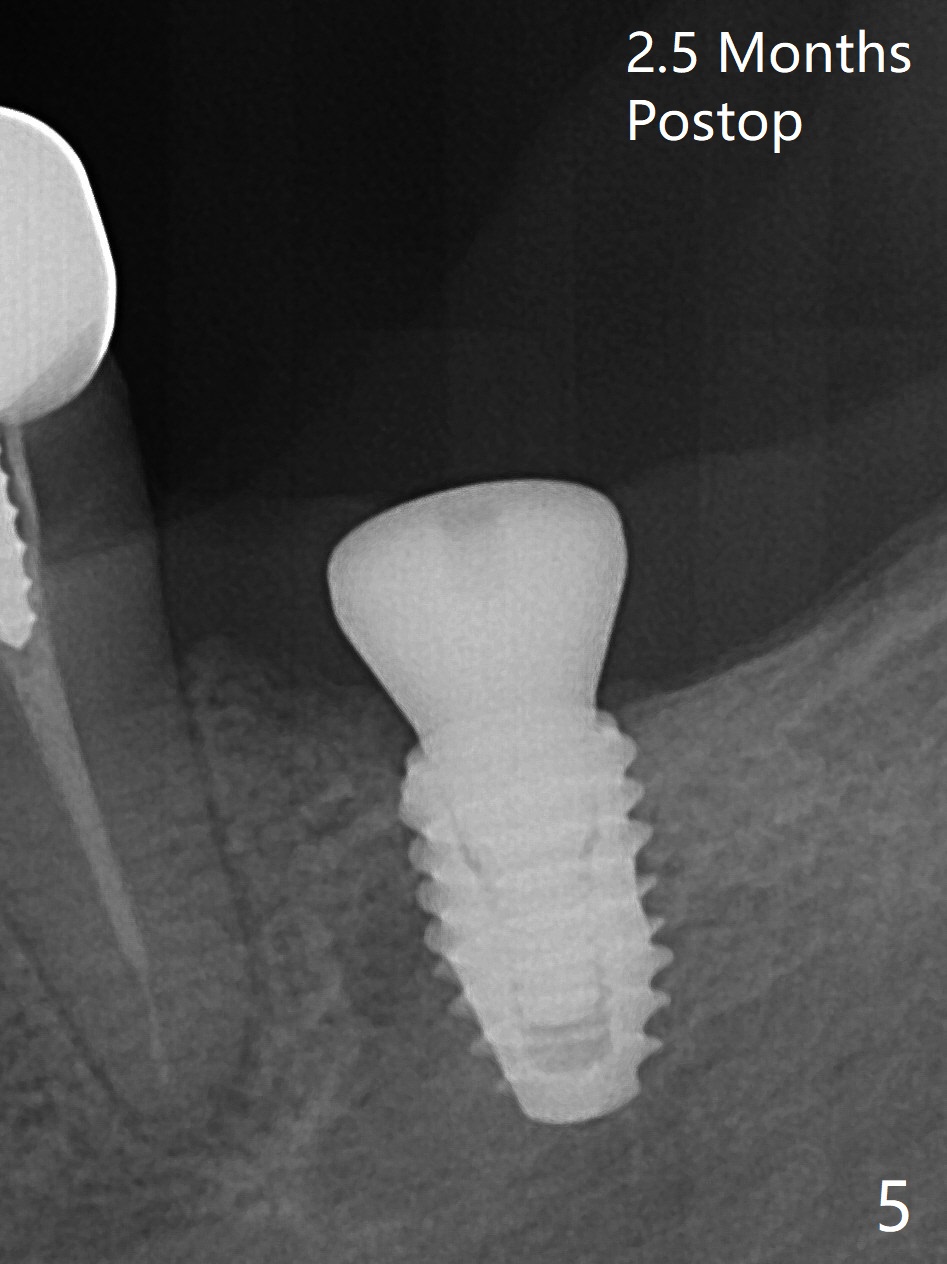

M

As a surgeon, I have never felt that my scalpel is as precise as media claims to be until guided surgery is introduced. The implants at #14 and 19 are placed as precisely as planned as well as painlessly and quickly (Fig.1-4). What else can we ask for? The gingiva around the healing abutment (5.5x3 mm) at #19 is erythematous (Fig.5). Later a longer healing abutment is used (Fig.6 (5.5x5 mm)). There is no bone loss 5 months or 7 months postop (Fig.6-9). The abutment screw is loose 3 months post cementation due to unfavorable crown/implant ratio (Fig.10); in fact the abutment is incompletely seated. Bicon implants will be in consideration to reduce screw loosening if implants are to be placed at #15 and 18. The abutment screw at #14 becomes loose 10 months post cementation; after retorque at #30 Ncm, the abutment is incompletely seated (Fig.11). It remains the same after use of 4.6 and 5.6 mm profile drills (Fig.12). A healing abutment is placed. When the patient returns, use planning kit and try to place a 5.2x5.5(2) cemented abutment. In fact it works (Fig.13). The crown at #19 is loose again 1 year 5 months post retightening. After removing crown/abutment, the mesial surface of the crown is heavily reduced. The crown/abutment is reseated to make sure that there is no proximal contact between the neighboring teeth (Fig.14 arrow). Because of tilt of the PA, it is difficult to tell the tightness of the contact between the implant and abutment, but the apical space is significantly reduced (*, as compared to Fig.10). Pick up impression is taken for porcelain addition occlusomesially. Two months later the patient returns for crown recementation. When the abutment is reseated with the repaired crown, the seating is incomplete (Fig.15). The abutment is completely seated when it is turned free hand with the flat surface of the abutment faces distal (Fig.16 D). The screw is torqued 20 Ncm before reimpression.